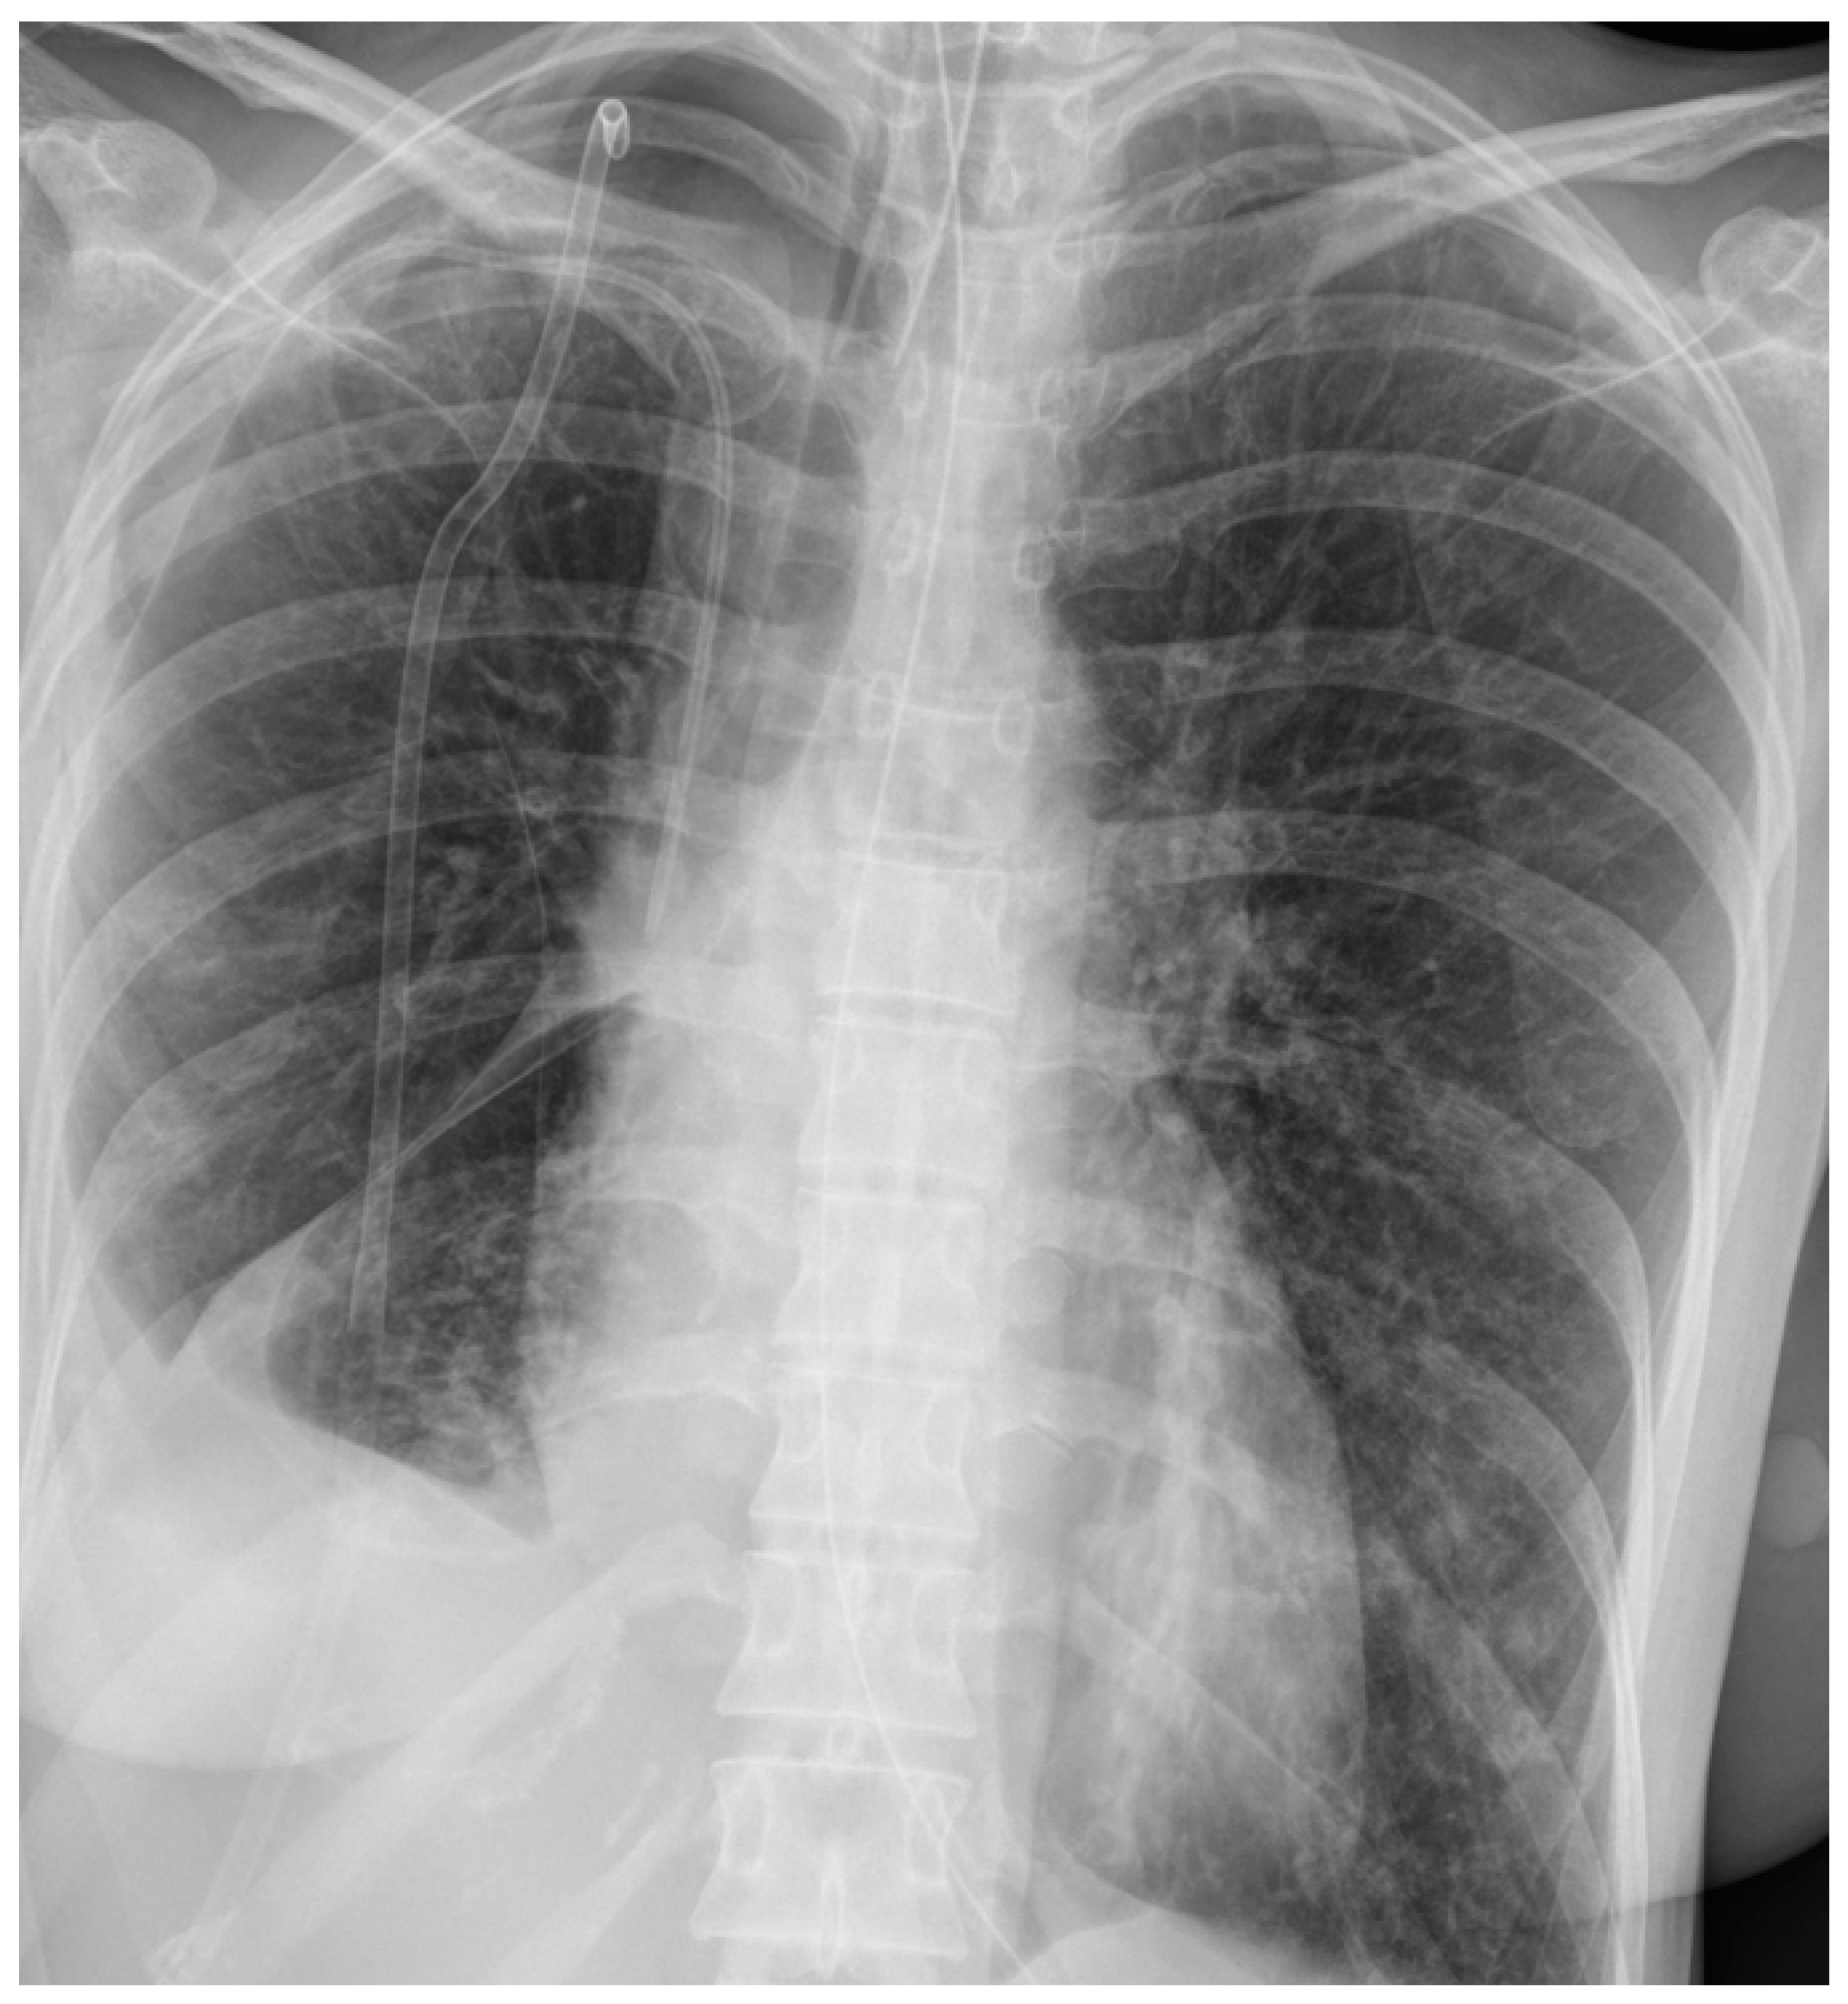

The first patient was a 36-year-old female who was initially hospitalized in the Department of Internal Diseases in the district hospital in a nearby city from day 1 to day 3 due to influenza infection. Her past medical history consisted of asthma and irritable bowel syndrome. She was admitted due to the worsening of respiratory symptoms despite antiviral treatment (oseltamiwir). On day 3, hemoptysis occurred, and decreased oxygen saturation was detected. Her clinical deterioration required admission to the ICU, where she was intubated and mechanically ventilated. Chest X-ray revealed right-sided pneumothorax, which was treated twice with pleural drainage—without the effect of lung expansion. She was then transferred for surgical treatment to the Thoracic Surgery Department in Zabrze due to suspected pleural empyema, lung abscesses, and pneumothorax with air leak. The chest X-ray performed at admission is presented in Figure 2.

Figure 2. Chest X-ray of patient 1 at admission to the intensive care unit.